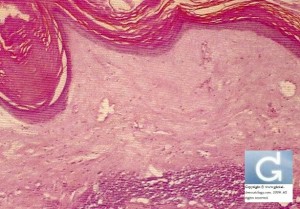

Lichen Scléro-atropique

- Lichen Scléro-atrophique (LSA): Papules d’aspect ivoire. Souvent localisé dans la région génitale

- Lichen Scléro-atrophique (LSA): l’histologie montre une atrophie de l’épiderme avec une sclérose hyaline du derme superficiel. On retrouve un infiltrat de lymphocytes.